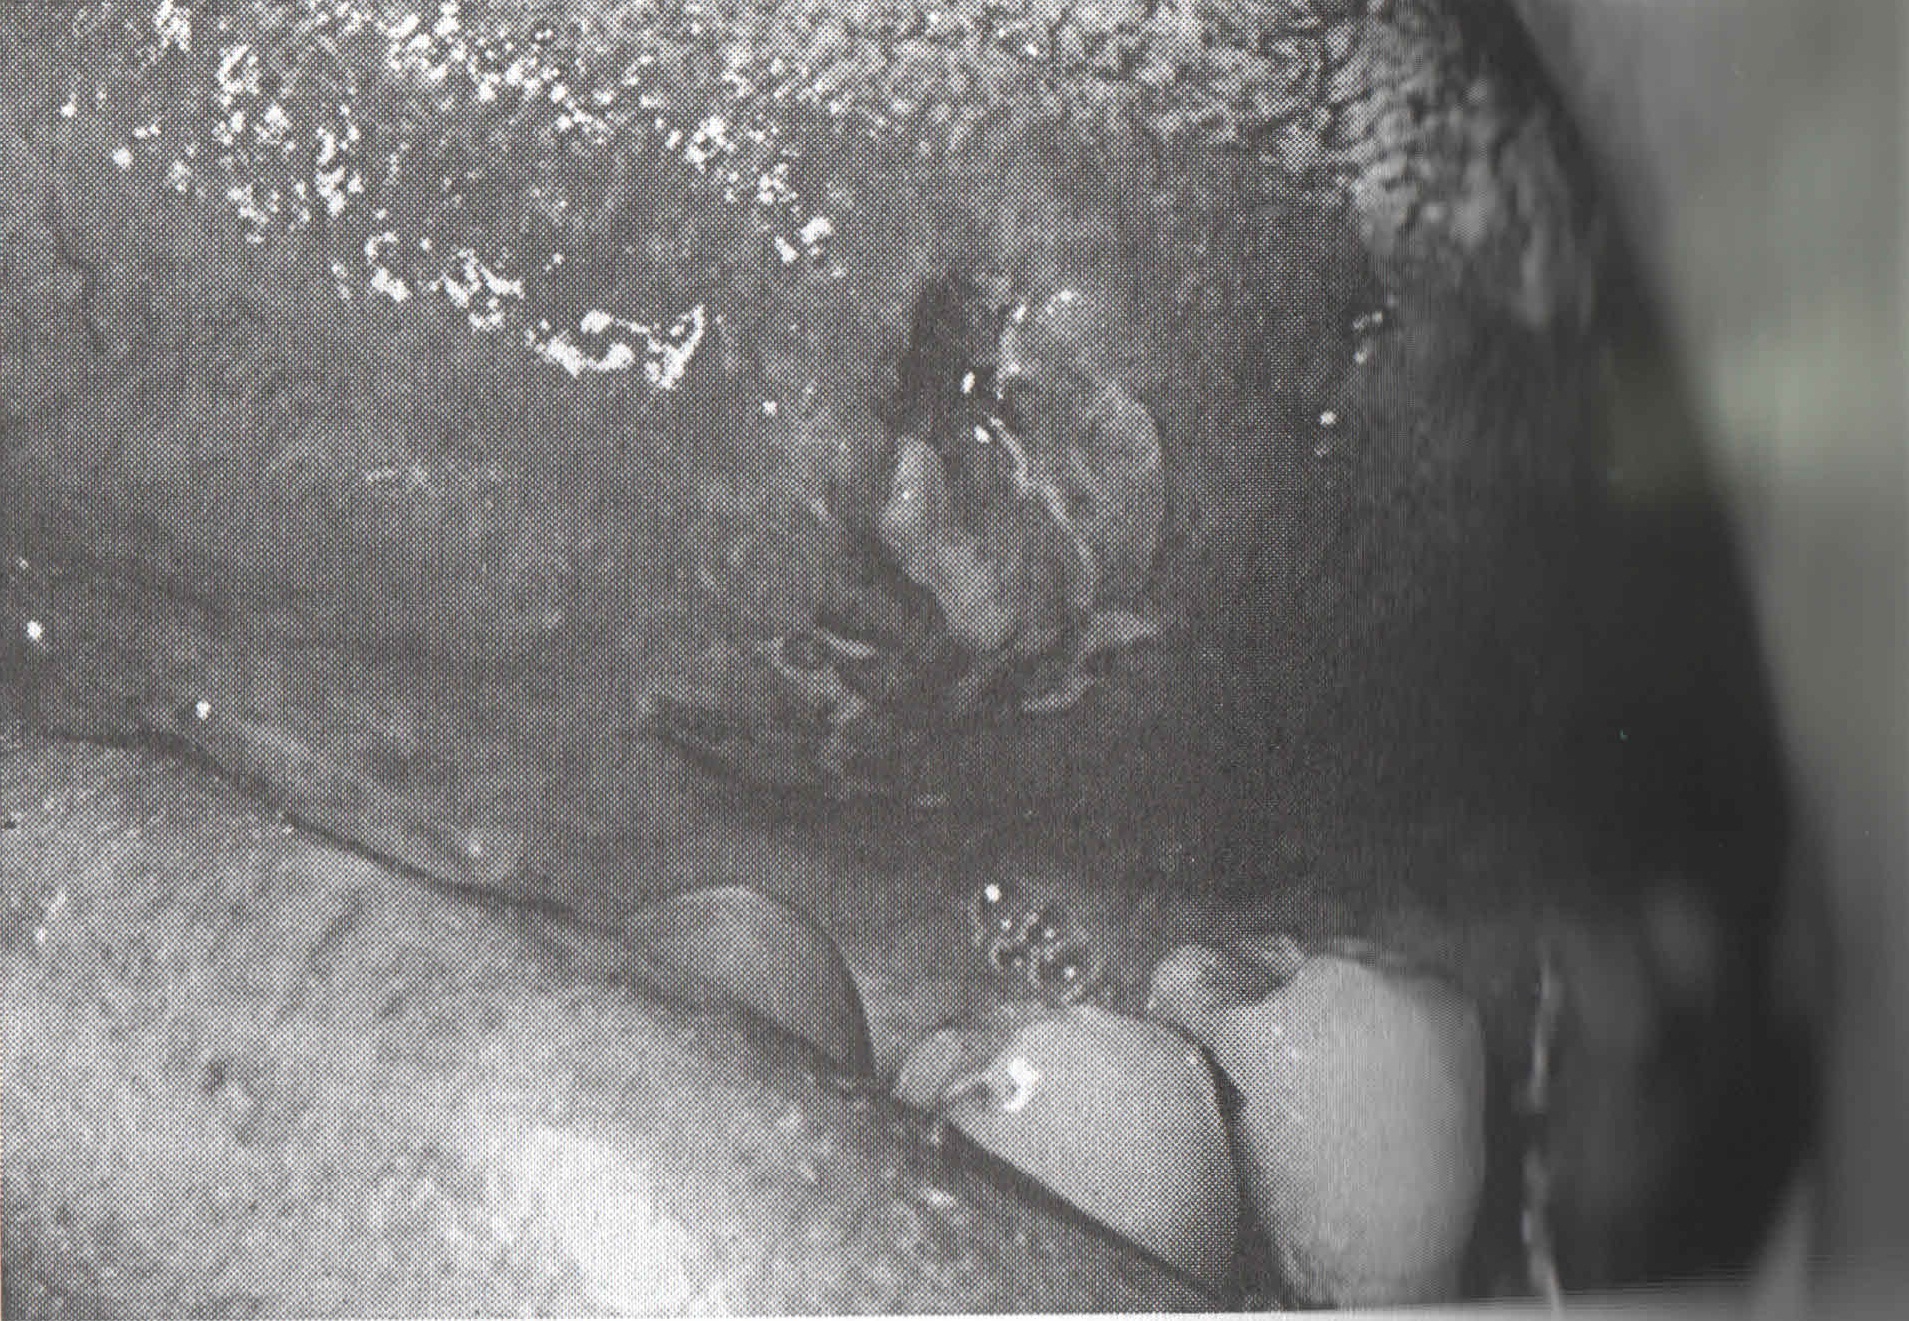

COCCIDIOMYCOSIS C. immitis daha sık görülmektedir. Akut olgularda titre yükselmektedir. Antikorlar, bazen bir yıla kadar ölçülebilmektedir. İnfeksiyondan sonraki ilk iki haftada, % 80 olguda ID test pozitif olabilmektedir. |